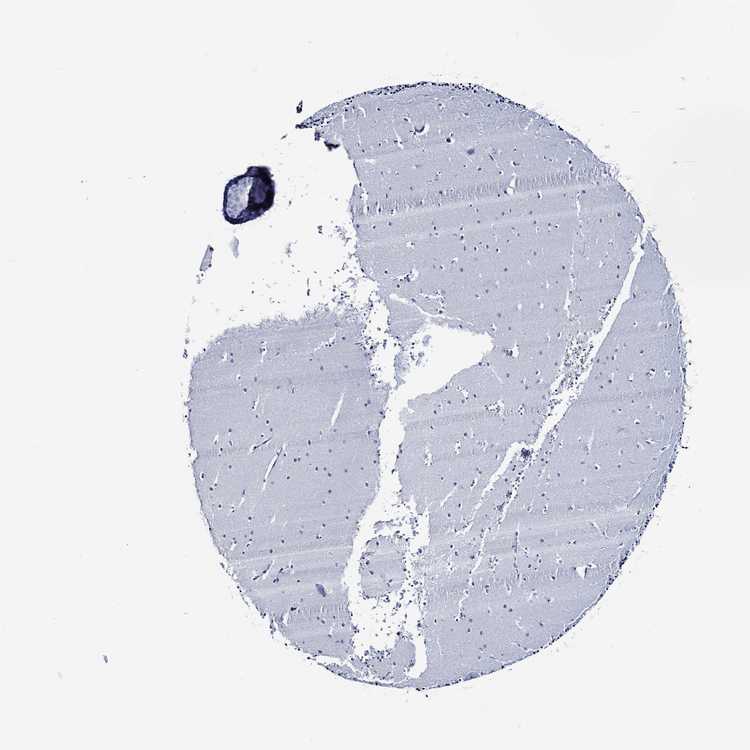

CEREBELLUM - Antibody stainingi

Antibody staining in the annotated cell types in the current human tissue is reported as not detected, low, medium, or high, based on conventional immunohistochemistry profiling in selected tissues. This score is based on the combination of the staining intensity and fraction of stained cells.

Each image is clickable and will lead to virtual microscopy that enables deeper exploration of all samples and also displays staining intensity scores, fraction scores and subcellular localization as well as patient and tissue information for each sample.

Antibody HPA043255Antibody HPA043639

Purkinje cells Not detectedNot detected

Cells in granular layer Not detectedNot detected

Cells in molecular layer Not detectedNot detected